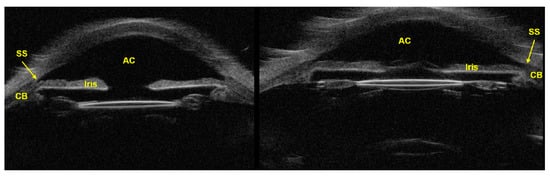

3.2. Ultrasound Biomicroscopy (UBM)

- Kapoor, R.; Parameswarappa, D.C.; Dhurandhar, D.; Peguda, H.K.; Rani, P.K. Peering into the eye: A comprehensive look at ultrasound biomicroscopy (UBM) and its diagnostic value in anterior segment disorders. Indian J. Ophthalmol. 2023, 71, 3118. [Google Scholar] [CrossRef]

- Patel, A.S.; Akkara, J.D.; DelMonte, D.W.; Morkin, M.; Murchison, A.; Alexander, J.L.; Giaconi, J.A.; Desai, M.; Sheybani, A.; Sollenberger, E.L. Ultrasound Biomicroscopy. Available online: https://eyewiki.org/Ultrasound_Biomicroscopy (accessed on 14 September 2024).

- Helms, R.W.; Minhaz, A.T.; Wilson, D.L.; Örge, F.H. Clinical 3D Imaging of the Anterior Segment with Ultrasound Biomicroscopy. Trans. Vis. Sci. Technol. 2021, 10, 11. [Google Scholar] [CrossRef] [PubMed]

- Mansouri, K.; Sommerhalder, J.; Shaarawy, T. Prospective comparison of ultrasound biomicroscopy and anterior segment optical coherence tomography for evaluation of anterior chamber dimensions in European eyes with primary angle closure. Eye 2010, 24, 233–239. [Google Scholar] [CrossRef]